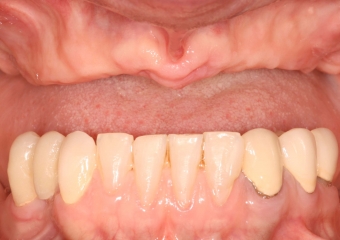

Prótese fixa em porcelana sobre implantes

Imagens da prótese fixa em porcelana e zircônia sobre implantes, do caso terminado em Fevereiro 2012